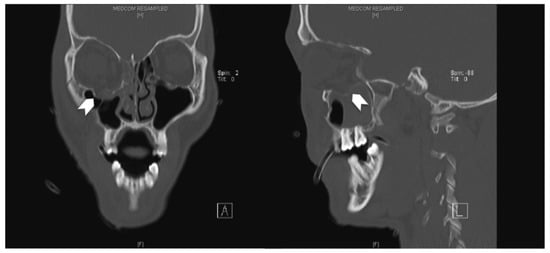

Case 2

A 66-year-old woman sustained a left ZMC fracture and orbital floor fracture following a fall (Figure 5), resulting in left enophthalmos and diplopia on upward gaze. She underwent ORIF and orbital floor reconstruction 12 days after the injury. Both the 0.4-mm titanium orbital mesh and orbital rim plate were used (Figure 6). Postoperatively, she complained of progressive worsening of left upward gaze diplopia, starting around 2 weeks postoperatively and worsening over 4 weeks. There was also dimpling noted over the left lower lid due to lid retraction; however, forced-duction test was negative. She was given lower eyelid scar massage, which was performed in an upward oblique fashion from medial to lateral, and steroid injections (8 IU of triamcinolone) into the lower eyelid. On the 9th week postoperative follow-up, she reported improvement of diplopia but still had lower eyelid retraction and a tugging sensation (Figure 7). She was then given 0.3 mL of hyaluronic acid (HA) filler (Restylane; Galderma, Lausanne, Switzerland) into the posterior lamella space to correct the lower eyelid retraction. She experienced immediate and sustained (at 1 month) relief of symptoms of tugging and eyelid retraction.

Figure 5. Coronal and sagittal cuts of the CT scan of the face (Case 2) demonstrating the presence of a large left orbital floor defect (arrows).